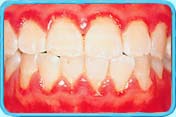

牙龈红肿及刷牙时牙龈容易出血。

图中所见是患有妊娠期牙龈炎的口腔情况,牙龈严重红肿,并有出血。